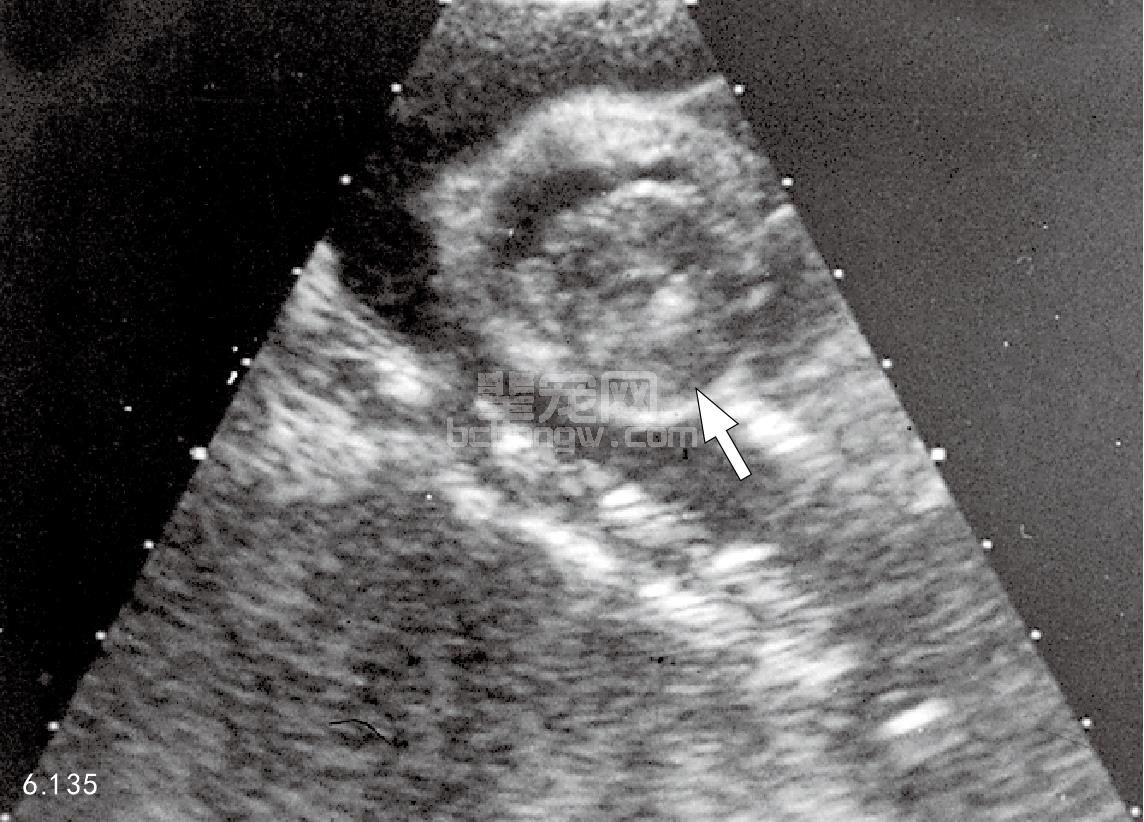

图6.135 患HCM的13岁猫,其二维右侧胸骨旁的超声波心动描记,显示典型的心室壁增厚(箭头所指)。

超声波心动描记术 HCM的特征有:对称性的,或较少不对称性的左心室壁和室间隔(舒张厚度大于 5.5mm)肥大,有时存在有高回声的大乳突状肌肉和左心房扩张。血小板可能存在于左心房壁上,左心室收缩和 舒张的内径降低,分级缩短是正常或增加。收缩前房室瓣膜运动可由M-型检测记录下来。如果动态的左心室外 流障碍存在,多普勒研究可显示房室瓣心脏口回流和/主动脉速率增加(图6.135~图6.137)。